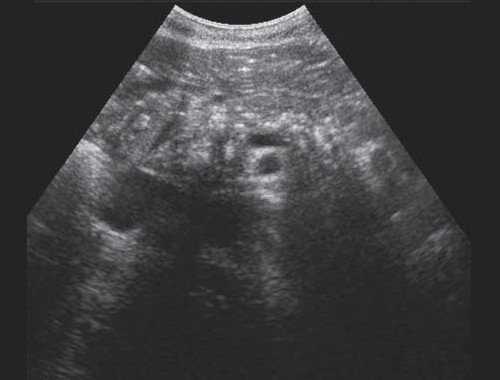

• УЗИ в черно-белом режиме

о Дилатация внутрипеченочных протоков

- Диаметр протоков > 2 мм

- Тубулярные анэхогенные ветвящиеся структуры, сопутствующие воротным венам:

Симптом «параллельного канала»

Зачастую самыми первыми из внутрипеченочных протоков расширяются протоки левой доли печени

- Расширенные протоки могут быть извитыми и иметь неравномерный просвет

- Проксимально у ворот печени сливающиеся тубулярные структуры формируют звездчатую структуру